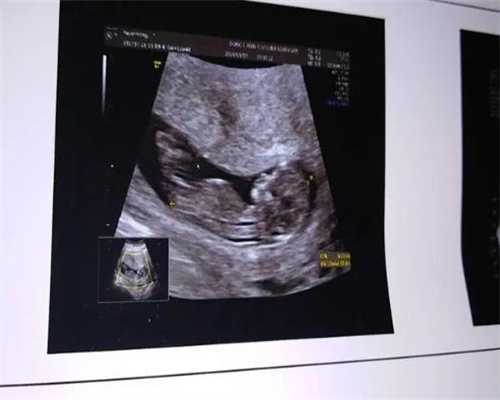

胎心率